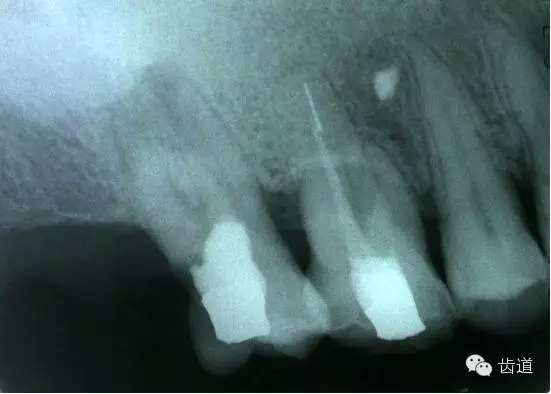

左上4鑄造樁側(cè)穿

左上7近中頰根器械折斷

右上6腭根器械折斷